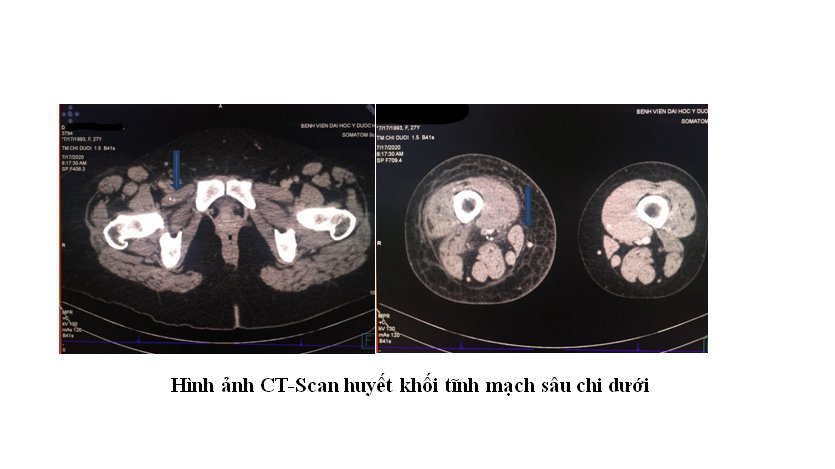

Bệnh nhân được cho nhập viện sau vài ngày và làm thêm các xét nghiệm nhưng chưa thấy rối loạn tăng đông máu. Nhận thấy đây là một bệnh nhân có nguy cơ cao với huyết khối tĩnh mạch sâu nên ekip điều trị đã sử dụng Enoxaparin (Thuốc chống đông máu Heparin trọng lượng phân tử thấp) để dự phòng huyết khối trong khi chờ thực hiện CT-Scan hệ tĩnh mạch chi dưới. Kết quả CT-Scan phù hợp với biểu hiện lâm sàng của bệnh nhân: Huyết khối tĩnh mạch sâu từ vùng cẳng chân phải lan lên tĩnh mạch chậu ngoài và chậu chung phải.